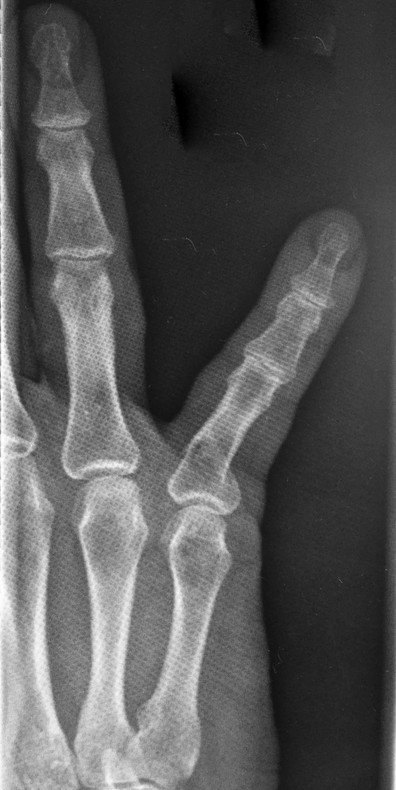

14.2 Salter-Harris 2 Fractures of the Proximal Phalanx

The most common type of Salter-Harris fracture involves fracture through the metaphysis of the proximal phalanx and it has an incidence of 80% (Fig. 14‑4). These injuries are very common in the emergency department and can easily be reduced using a pen as a fulcrum (Fig. 14‑5).

In older children, this manipulation can be done under local anesthetic and checked with fluoroscopic scan; otherwise, general anesthesia is needed. After reduction, the adjacent finger is buddy strapped to the injured finger and the hand is rested in a volar splint before active mobilization at 1 week.